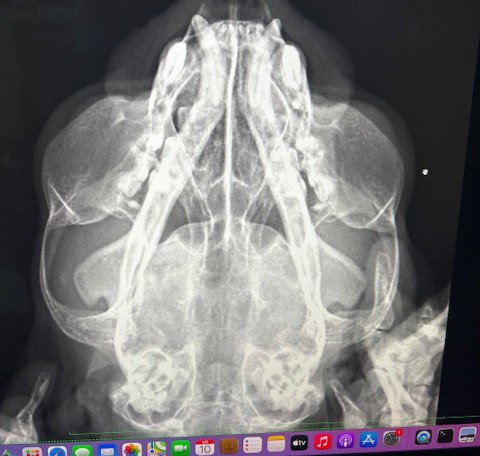

初めは最近くしゃみが増えたかな、と思っていたところ突然鼻が詰まり口で呼吸をし始め、翌日には鼻血がみられるようになりました。鼻が詰まってからはごはんも全く食べれなくなりました。X線で鼻腔内に腫瘤を疑う影が見られ、CT検査+組織生検を行ったところ、鼻腔内のリンパ腫が診断されました。